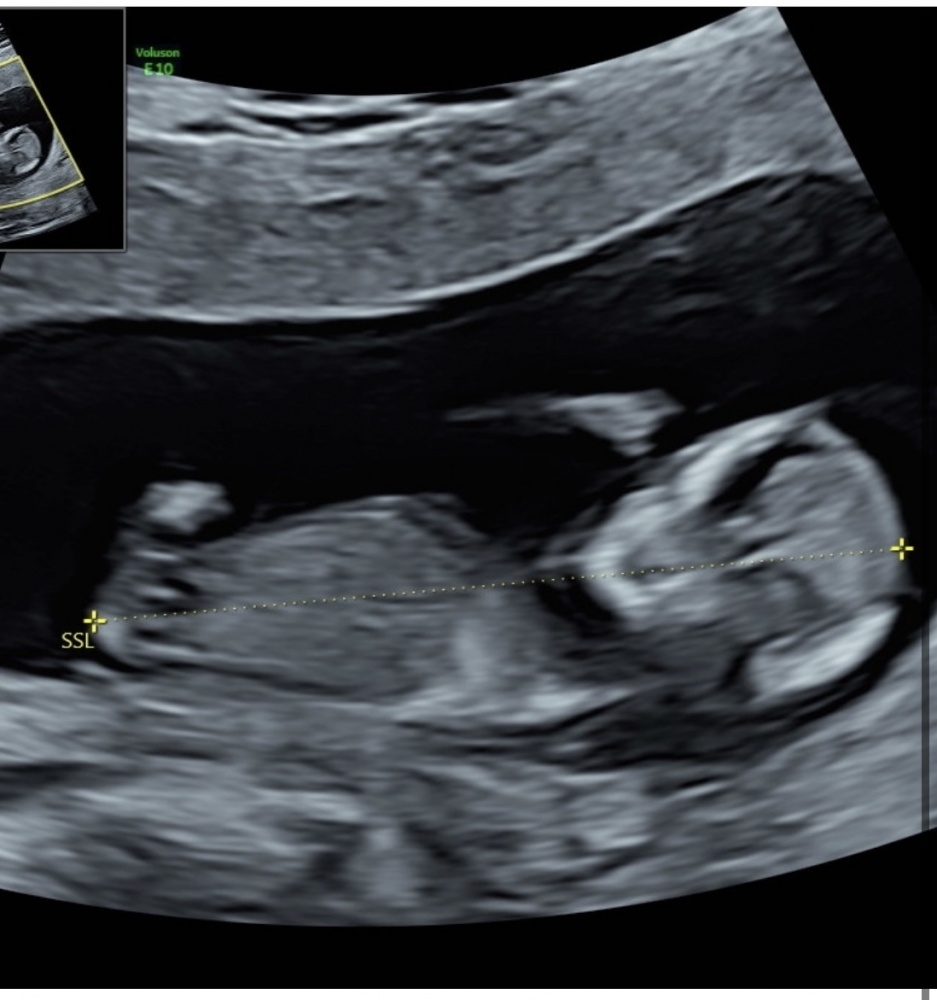

Ärztin meinte gestern bei der nackenfaltenmessung sie kann Geschlecht sehen darf es aber nicht sagen weil ich erst 13+1 bin und hat mir aber ein Bild mit gegeben. Kann von euch jemand was erkennen?

Ich hätte ja Mädchen getippt aber mein Frauenarzt meinte letztens noch junge und ich dachte ich habe auch eindeutig einen jungen gesehen auf dem us gerät. Jetzt bin ich so verwirrt 😱jm3n23qzymiy.jpeg